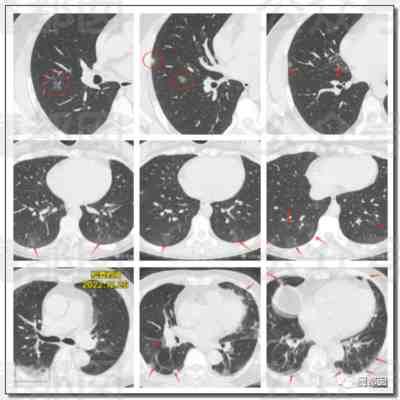

这个我们在过去几天的文章中写过多次,我们好像是所有公众号里最早写这波肺炎的,今天再给大家一个案例,这批肺炎总量还真的不小:

第三,对于新冠而言,可以达到群体免疫屏障?不可能!